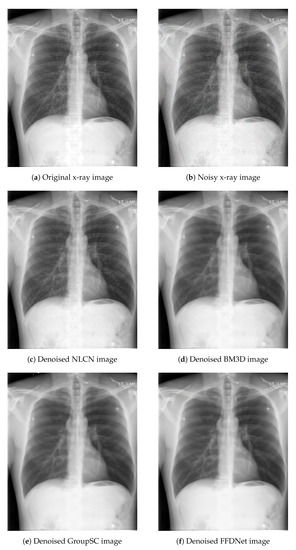

The network used for this problem makes use of a 2-column architecture, the output of which is concatenated in the end. One column basically provides an output based on the combination of input data, weighted by positive coefficients. This works as a non-linear low-pass filter. The other column adopts a different normalization function, hence providing both positive and negative coefficients. This is particularly suitable for realizing high-pass non-linear filters. We have used Poisson noise, Gaussian noise and a combination of Poisson and Gaussian noise for verifying the results on the X-ray images. Only Poisson noise on both grayscale and color images are used for natural scene images. We have used the popular BM3D filter, as well as a couple of CNNs as a baseline to compare our results both visually and using objective scores via SSIM and PSNR. Such metrics have been adopted taking into consideration that they are widely used in the literature as a standard measurement metrics for these tasks. It should be noted that non-linear convolution-based kernels have not yet been applied for noise reduction tasks, to the best of our knowledge. We have taken FFDNet [24] and GROUP-SC (G-SC) [25] as NN bases to compare performances on the X-ray and LIVE datasets. The parameter settings for the NLCN are the same for all experiments. Both the NLCN and FFDNet have a faster inference time (less than one second per image) when compared to BM3D and Group-SC. Group-SC has the highest average inference time of approximately 77 s per image for color images and 34 s per image for grayscale images. However, the number of trainable parameters for Group-SC are lower (approx. 112 K) than both FFDNet (553 K) and NLCN (414 K). It is observed that the NLCN obtains overall competitive results. It provides a superior performance on X-ray images when compared to the other NNs. Performance of these networks on Gaussian noise is particularly low. An example of these images is shown in Figure 9 and Figure 10. It can be observed that the BM3D filter and the NNs do a very fine job in removing noise from the natural as well as X-ray images. However, for BM3D, in both cases the images are over-smoothed. The FFdNet and Group-SC work better on natural images, but oversmooth the X-ray images. This is also reflected in the SSIM and PSNR scores shown in Table 2. It should be noted that the main purpose of these experiments was to demonstrate that the network is suitable for a wide range of tasks. Particular performance enhancement and robust comparison with several state-of-the-art techniques is not a part of our scope and can be obtained by changing different parameters such as kernel sizes, number of filters etc.

Figure 9.

Application of denoising on X-ray images.